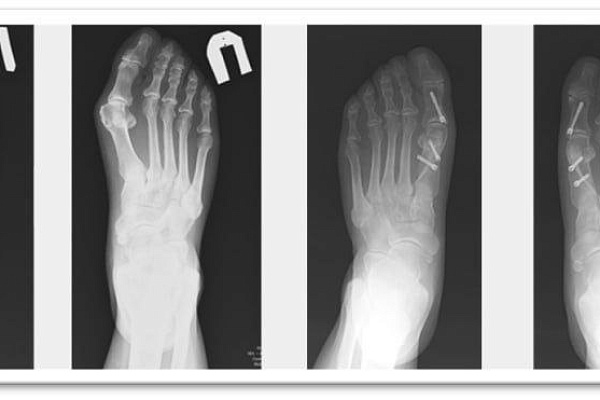

-Высокотехнологичные фиксирующие элементы не требуют удаления и не доставляют неудобств в дальнейшем. Они не мешают таким исследованиям, как МРТ, на них не реагируют рамки досмотра и металлоискатели. Имеющаяся линейка винтов позволяет выполнять фиксацию при самых сложных деформациях. Причем, даже пожилым женщинам с хрупкими, пораженными остеопорозом костями. Например, недавно мы успешно избавили от запущенной проблемы 76-летнюю пациентку. Ей провели 11 корригирующих остеотомий в ходе одной операции. Такой большой объём вмешательства обусловлен деформацией всех пальцев стопы и необходимостью вернуть каждый в правильное анатомическое положение, - объясняет заведующий отделением травматологии и ортопедии №1 Сергей Глиняный.